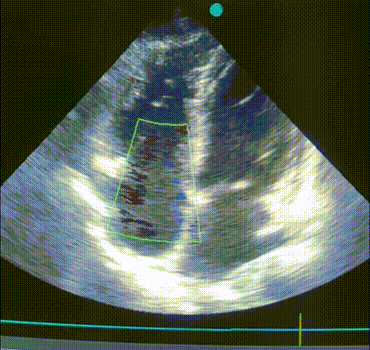

ЕхоКС (7 день):

![]() |

|

A4CH, кольоровий допплер. Зверніть увагу на регургітацію на ТК. |